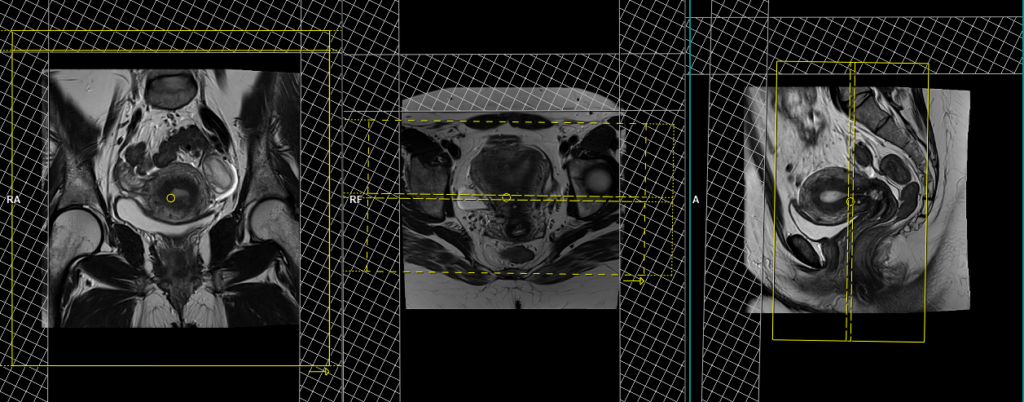

T2 tse axial 6 mm largeFOV

Plan the large field of view (FOV) axial slices on the coronal plane, position the block parallel to the line along the right and left iliac crest. The positioning block should also be checked in the other two planes. An appropriate angle needs to be established in the sagittal plane, which is perpendicular to the lumbar spine. The slices must be sufficient to cover the entire lower abdomen and pelvis, ranging from the middle of the kidneys down to the symphysis pubis. The FOV should be large enough to cover the entire pelvis, typically ranging from 350mm to 400mm. Adding saturation bands on top of the axial block can help reduce artifacts caused by arterial pulsation and breathing. Large FOV scans are usually performed to evaluate the para-aortic and pre-sacral nodes.

Parameters

TR 5000-6000 | TE 100-120 | SLICE 6 MM | FLIP 130-150 | PHASE R>L | MATRIX 384X384 | FOV 350-400 | GAP 10% | NEX(AVRAGE) 2 |

T2 stir coronal 5 mm LARGE FOV

Plan the large field of view (FOV) coronal slices on the sagittal plane and position the block parallel to the lumbar spine. The positioning block should also be checked in the other two planes. An appropriate angle needs to be established in the axial plane, which runs parallel to the right and left hip joint. The slices must be sufficient to cover the entire abdomen and pelvis, ranging from the anterior abdominal wall to the sacrum. The FOV must be large enough to cover the abdomen and pelvis (typically 380mm-400mm). Large FOV scans are usually performed to evaluate the local spread of the pathology and assess the para-aortic and pre-sacral nodes.

TR 4000-6000 | TE 110 | FLIP 160 | NEX 2 | SLICE 5MM | MATRIX 384X320 | FOV 380-400 | PHASE R>L | GAP 10% | TI 150 |